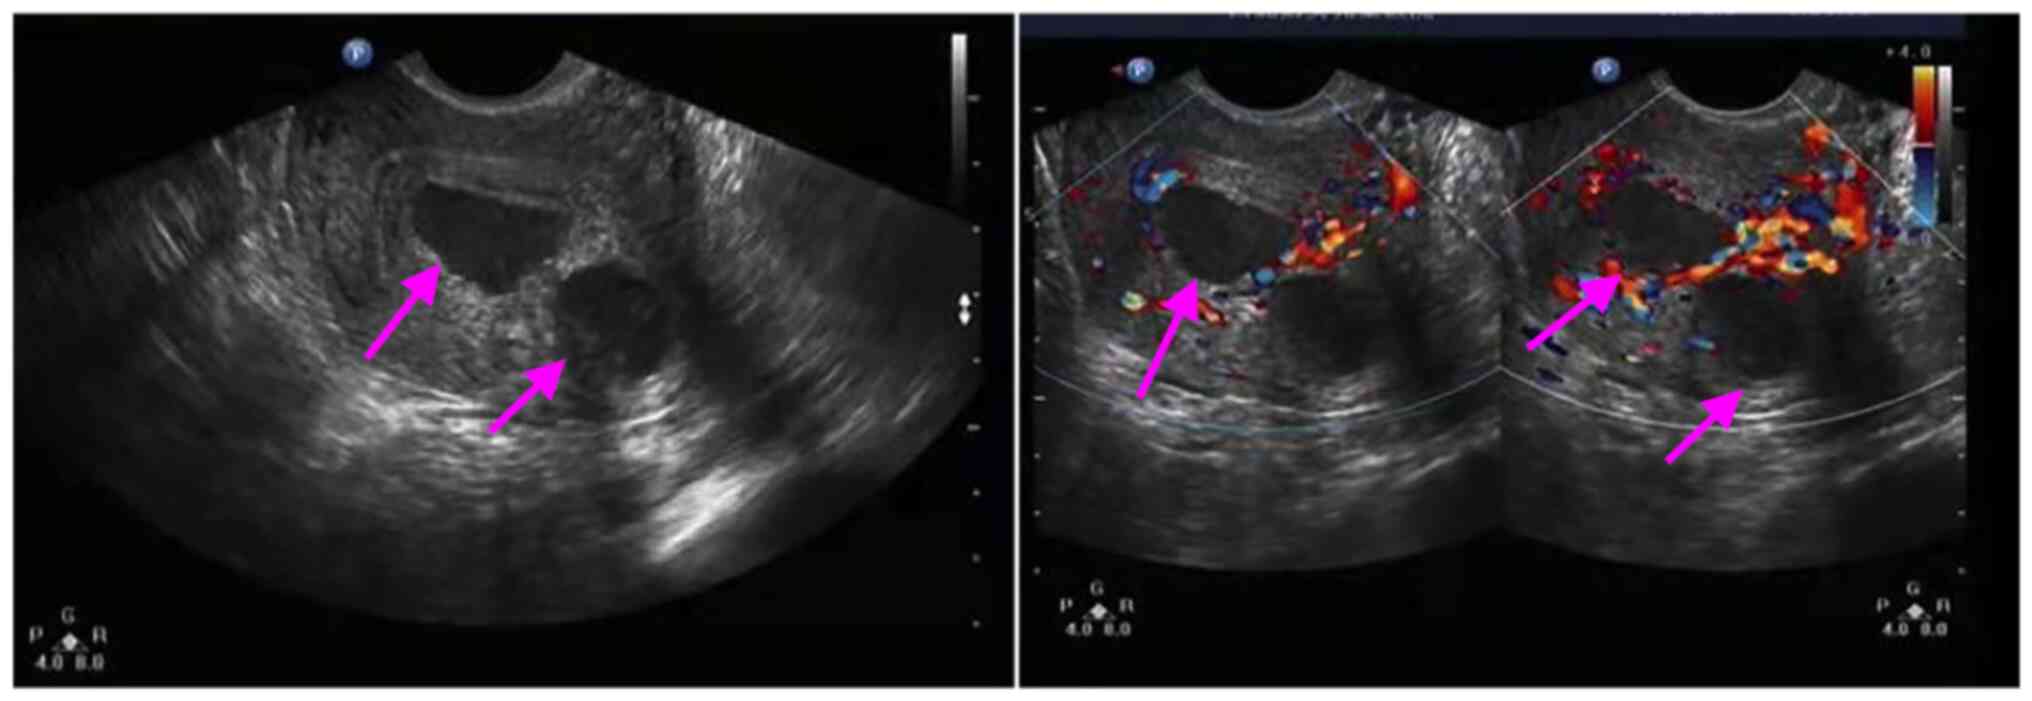

Ultrasonic examination. Ultrasonography displayed a multi-locular cystic mass on the posterior wall of the uterus. Color power Doppler revealed a difference from a leiomyoma. The mass was diagnosed as uterine adenomyoma (Fig. 1). The ultrasound of the hepatobiliary duct, pancreas and spleen exhibited no abnormalities. An abdominal CT scan indicated no abnormal density lesions in the liver, bile duct, pancreas, spleen or gastrointestinal tract.

Figure 1

Transvaginal ultrasound scan of the uterus indicating the lesion with an adenomyotic cyst (the left panel arrows). Doppler flow examination (right panel) demonstrated blood flow to the lesions (arrows).